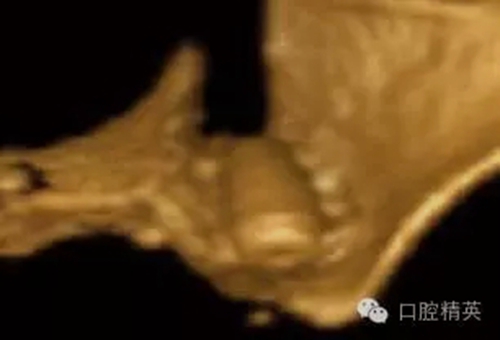

圖5a:一個失敗的種植體修復體的口內近面觀,25號牙根方頰側骨板裂開,粘膜穿孔。

圖5b:術后對25號牙區(qū)域進行iCAT CBCT斷層片成像診斷,其結果揭示了種植體和其周圍解剖結構的頰舌向位置關系,顯示嚴重的頰側骨板缺如,至少三分之一的頰側螺紋暴露。

圖5c:CBCT三維立體效果再現(xiàn)顯示了25號牙處嚴重的頰側骨板裂開。

頰側骨板裂開或穿孔(圖5a-c)